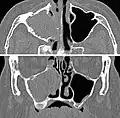

Maxillary sinusitis caused by a dental infection associated with periorbital cellulitis